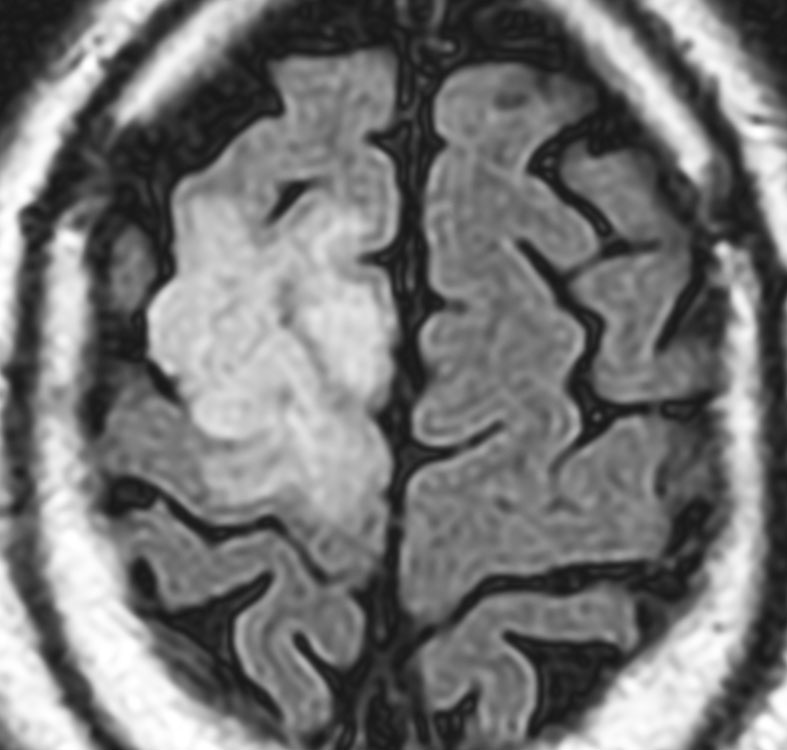

若い成人です,認知機能障害で発症しました。この画像を見るからに悪性神経膠腫,少なくともグレード3のグリオーマであることは明白です。しかし,グレード4膠芽腫あるいはグレード3退形成性星細胞腫にしては腫瘍周辺浮腫が軽すぎます。ですから,グレード3の退形成性乏突起膠腫 AO かも。認知機能の回復と温存を考量して,脳梁損傷と前交連損傷を避けて,右上前頭回と帯状回腫瘍を摘出しました。

左は術後のT1強調ガドリニウム増強像で,残存腫瘍がわかります。この腫瘍に対してICE (IFO/CDDP/VP-16) 化学療法を1コースしました。右側のMRIが1ヶ月後の画像です。このように1p/19q欠失のある退形成性乏突起膠腫は,化学療法感受性がとても高い悪性グリオーマです。ですから,手術で後遺症を残さないように,勢い込んで腫瘍を摘出しようとしないことが大切です。光顕診断はAOで,後々の解析で1p/19q codeletion でした。